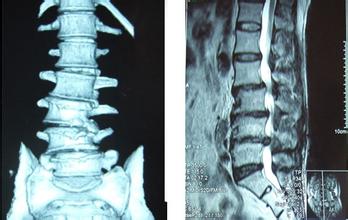

腰椎管狭窄了要怎么做功能锻炼?腰椎管狭窄多是因为自身腰椎病变或者遗传因素引起的,会使得椎管腔内变窄,刺激到周围的神经根,会引起腰部疼痛、肿胀等等。因此出现腰椎管狭窄了可以进行相应的功能锻炼,以缓解病痛。 >>>如果预防不当引起腰椎管狭窄危害健康了,该怎么治疗好?点击咨询

做好功能锻炼的同时,还要积极做好的治疗,这样效果才能更好。治疗腰椎管狭窄,可以使用德国椎间孔镜技术。德国椎间孔镜技术是目前治疗椎间盘突出的先进微创疗法之一,是同类手术中对病人创伤较小、效果较好的腰椎间盘突出微创治疗手术。该技术通过高清镜头成像、对腰部病变进行探查,并利用成套的微型器械部分摘除突出的髓核或肥厚的黄韧带,对破裂的纤维环进行修复,深入解决各类腰椎疾病。 >>>说说自己的病情,与在线医生进行一对一交流